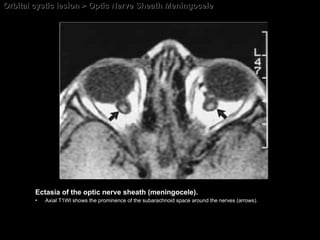

Optic Nerve Sheath Meningocele The CT and MR imaging; Prominent focal or segmental enlargement of the dural arachnoid sheath around the optic nerve  May be associated with an empty sella. May be associated with enlarged subarachnoid cisterns (optic nerve sheath cyst, arachnoid cyst, perioptic hygroma, and dural ectasia)

Orbital cystic lesion > Optic Nerve Sheath Meningocele Ectasia of the optic nerve sheath (meningocele).  Axial T1WI shows the prominence of the subarachnoid space around the nerves (arrows).